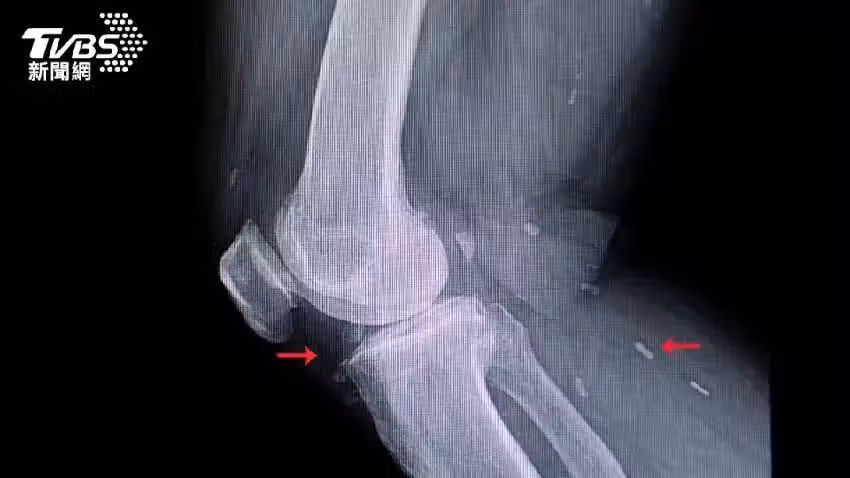

患者因為吃下沒煮熟豬肉,感染了「囊蟲病」,接受CT掃描時,體內布滿了寄生蟲死後留下的鈣化囊腫。

醫師加利26日PO出患者的CT掃描照,並在社群平台X表示,「這是我看過最瘋狂的CT掃描之一。

根據《每日郵報》報導,絛蟲的幼蟲可能進入肌肉甚至大腦等組織,它們被身體的免疫系統殺死後,會形成硬化的囊腫,在皮膚下可以摸到像腫塊一樣,在醫學掃描中會呈現出如白色橢圓形的「米粒」。